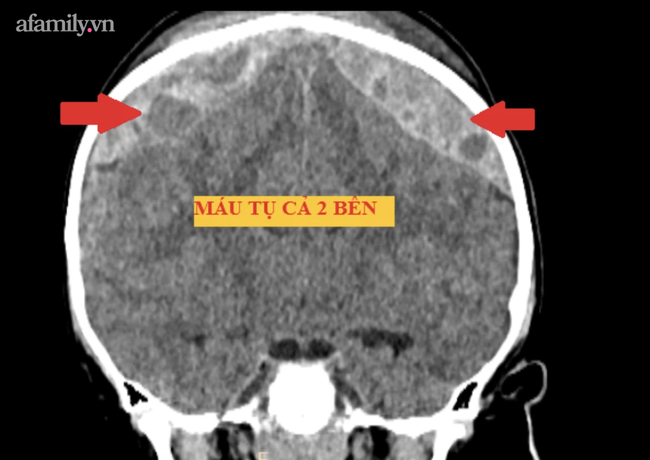

Ở khoa Cấp cứu, bé bắt đầu giảm tri giác, da đầu sưng rất nhiều kèm đau đầu. Bệnh nhi được chụp cắt lớp kiểm tra lại, phát hiện xương sọ bị bể kèm chảy máu trong hộp sọ nhiều, chèn ép não.

Ca mổ được tiến hành ngay trong đêm, lấy ra hơn 200ml máu giải phóng chèn ép não và cầm máu để ngăn ngừa chảy máu tái phát.

Bác sĩ Nguyễn Ngọc Pi Doanh, phẫu thuật viên chính ca mổ cho biết đây là trường hợp chấn thương sọ não nặng, phức tạp do vùng chấn thương nằm cả 2 bên, toác khớp sọ dọc giữa.

Lượng máu chảy nhiều và vị trí chảy máu nằm ngay xoang dọc trên, có nguy cơ chảy máu ồ ạt và bệnh nhi có thể tử vong nếu không kiểm soát được. Xương sọ bị toác đôi có thể do bé té cao, máu chảy nhiều từ xoang tĩnh mạch đúng như dự đoán.

Sau hơn 2 giờ phẫu thuật, ca mổ hoàn thành như dự trù. Hậu phẫu 2 ngày, tri giác cháu đã tỉnh táo, phim chụp kiểm tra lượng máu chảy đã được lấy hết và não đã được giải phóng khỏi chèn ép.

Bác sĩ cho biết nếu can thiệp trễ, bệnh nhi có khả năng tử vong do máu tụ chèn ép gây tụt não.